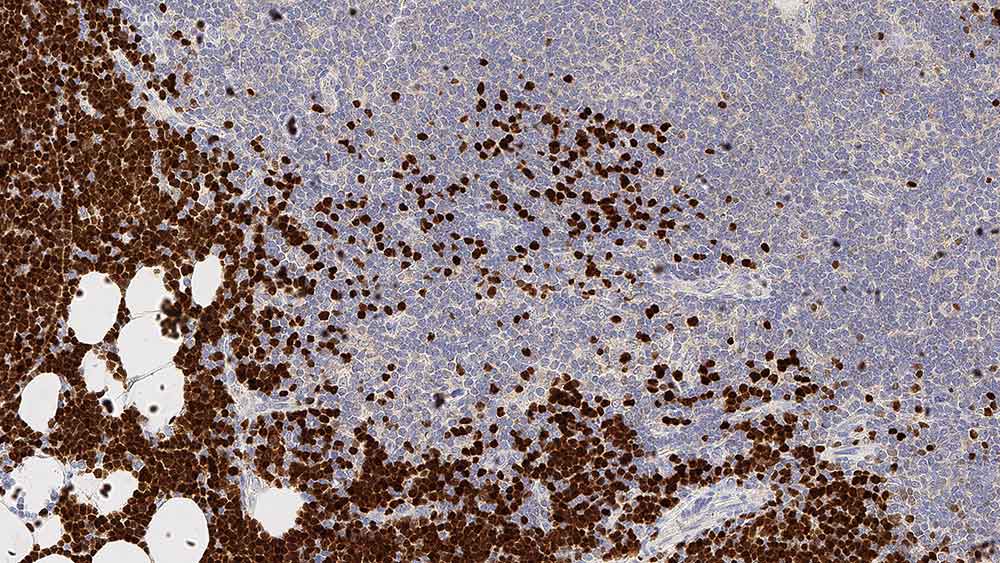

IHC-P analysis of human thymus tissue using GTX01873 TdT antibody [SEN28]. Note nuclear staining for cortical thymic lymphocytes.